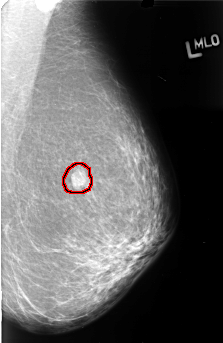

FILE: B_3410_1.LEFT_MLO.OVERLAY

TOTAL_ABNORMALITIES 1

ABNORMALITY 1

LESION_TYPE MASS SHAPE OVAL MARGINS OBSCURED

ASSESSMENT 3

SUBTLETY 5

PATHOLOGY MALIGNANT

TOTAL_OUTLINES 1

BOUNDARY